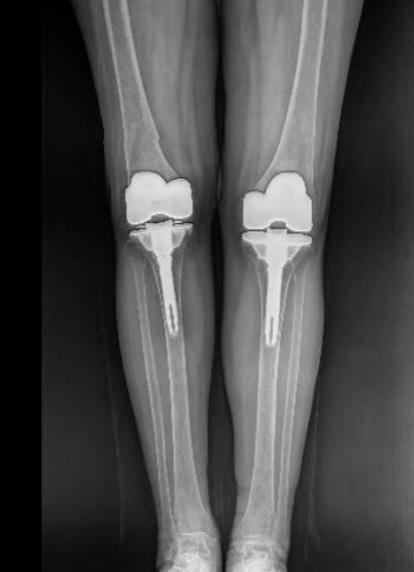

手术关键难点在于精准截除融合骨组织、获得屈伸间隙平衡、恢复下肢力线、确保韧带平衡以重建膝关节功能。团队凭借丰富经验和娴熟技术,成功实施双侧人工全膝关节置换术。术后影像学检查显示,假体位置精准,下肢力线完美纠正,原本僵硬关节被活动自如的人工关节取代,患者功能恢复理想,能正常行走,生活质量显著改善。

术后,刘阿姨来院复查,双膝功能恢复良好,关节屈伸自如,但在行走时,医生团队发现左下肢仍存在轻度跛行状态,进一步检查发现,左髋关节已出现纤维性强直,活动度不足30度,髋关节功能受限,建议尽早接受手术治疗,避免因行动不便出现跌倒意外。刘阿姨对当前“来之不易”的行走能力已经非常满意,便婉拒了医生提议。